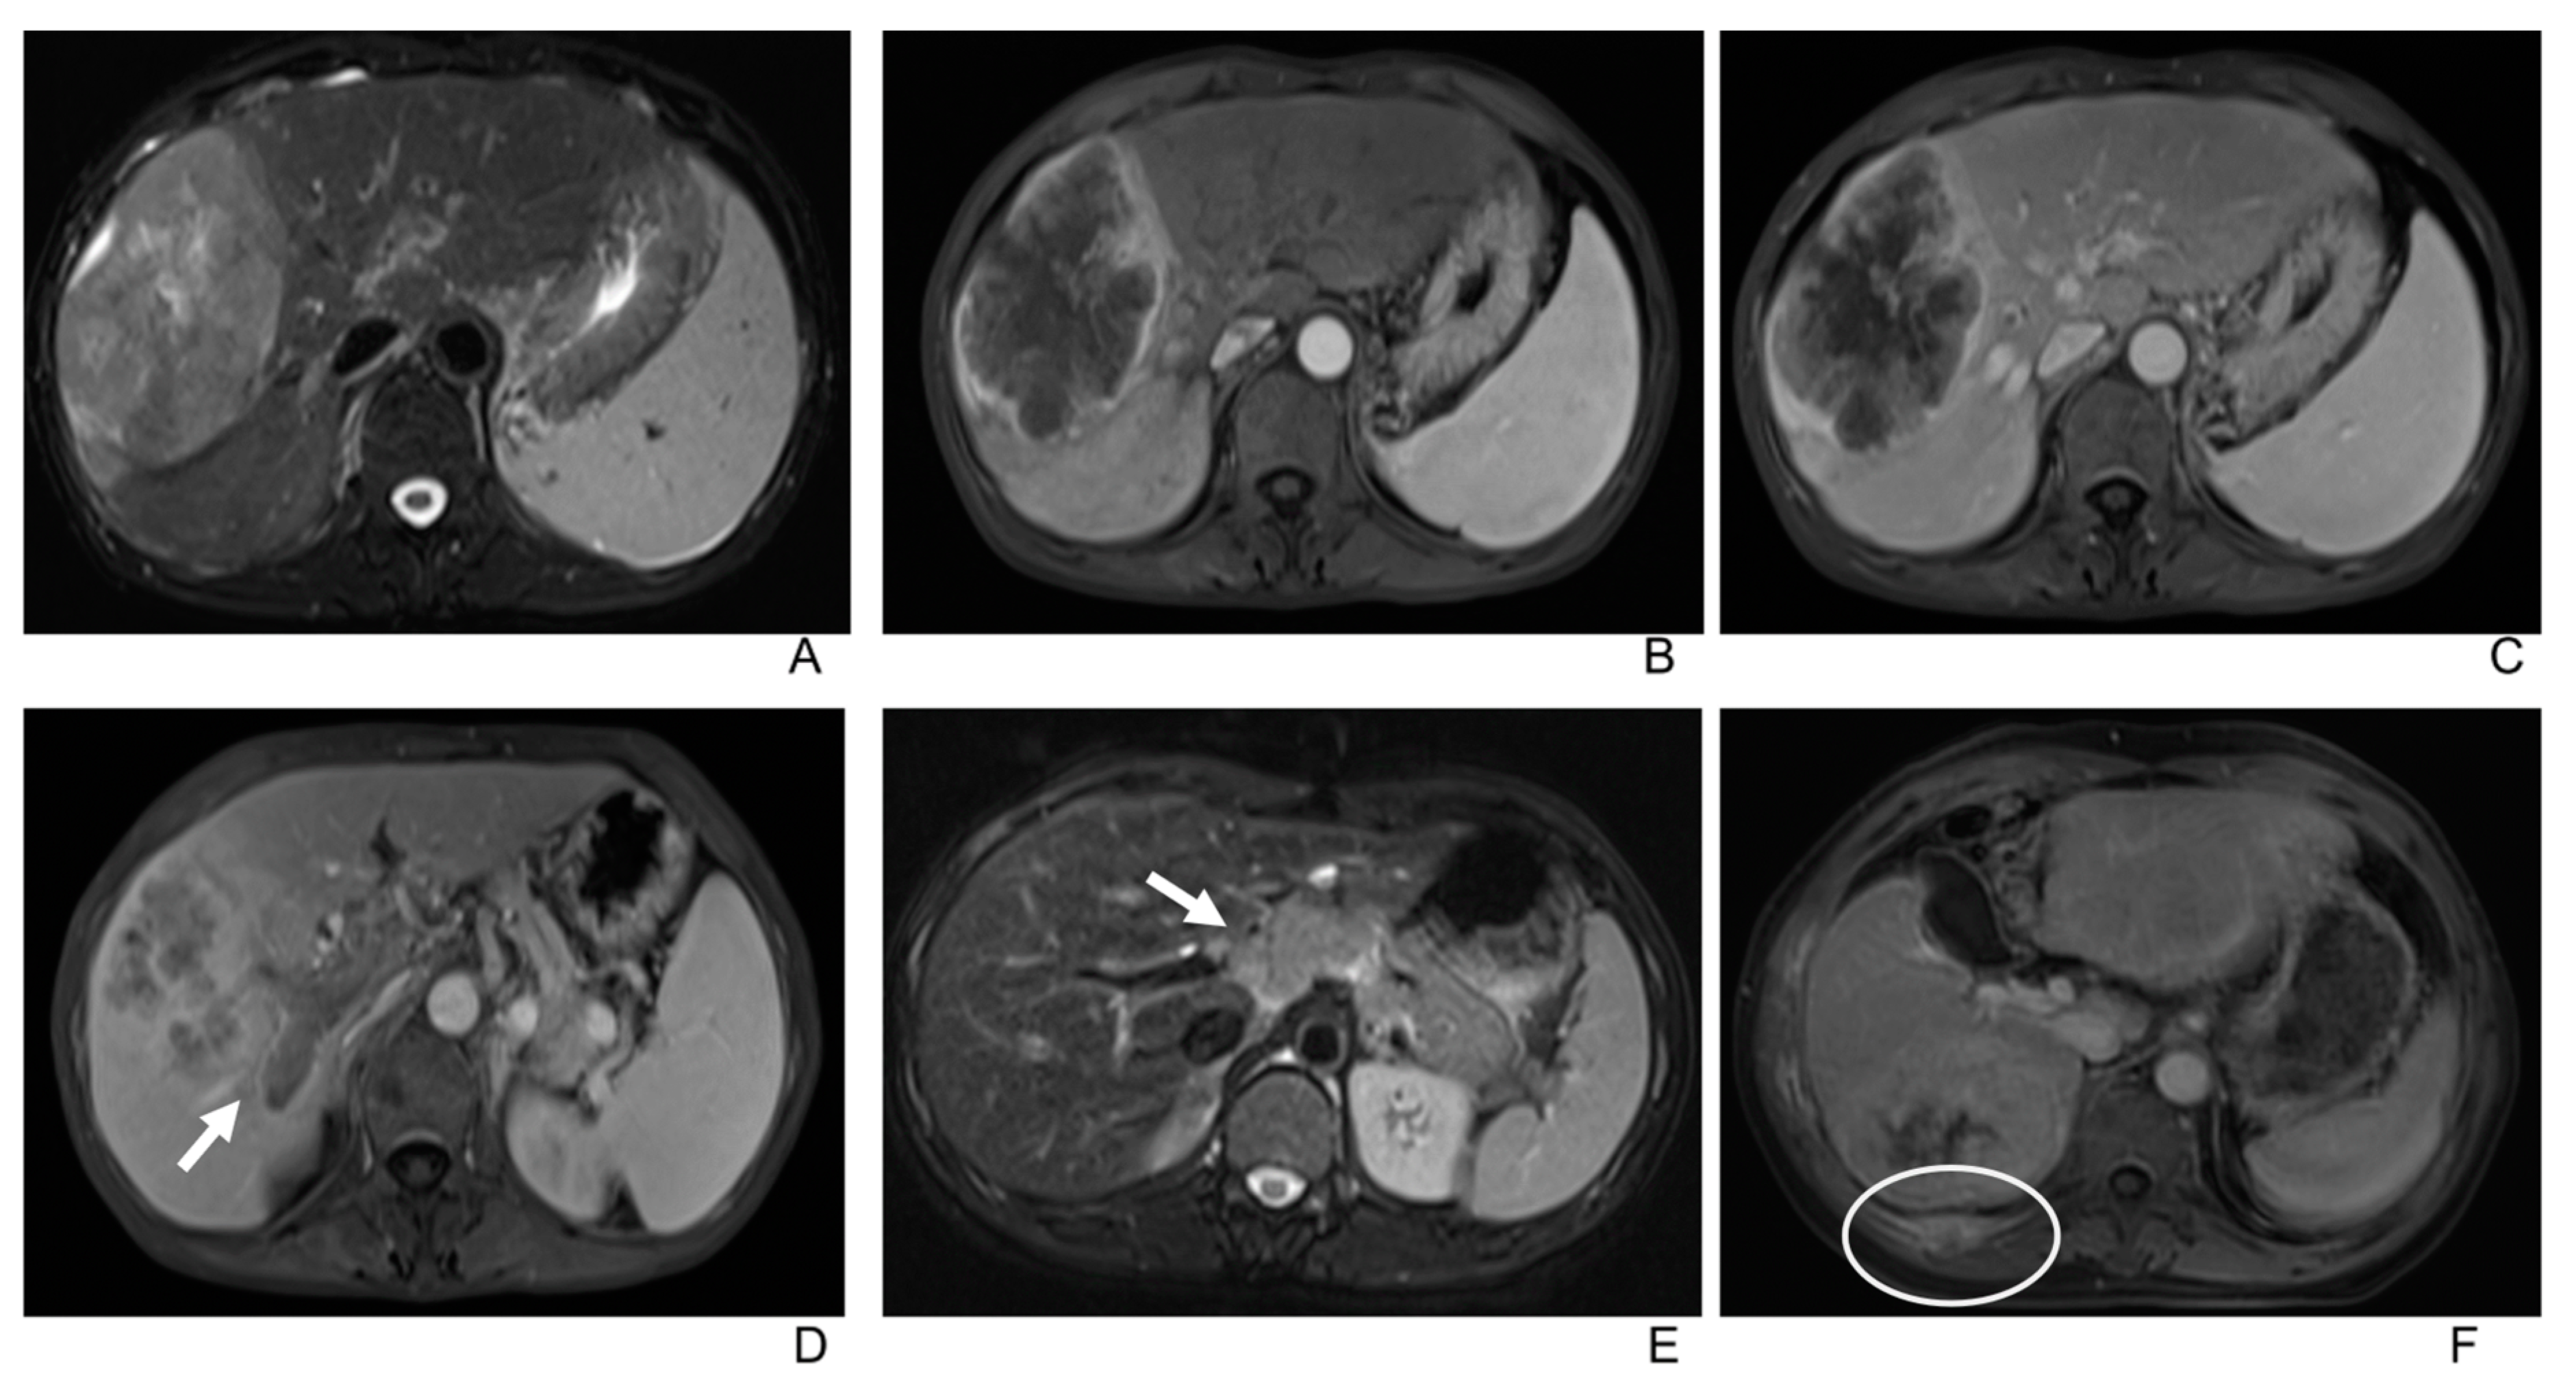

3.2. Imaging Manifestations

- Only two lesions showed a scar-like enhancement in the tumor in AP.

| In peripheral subcapsular region | 22 (58%) |

| Tumor shape (round, oval, or irregular) | (16/11/11) |

| Lesion contour | |

| Well defined | 25 (66%) |

| Obscure | 13 (34%) |

| Appearance of liver capsule | |

| Bulging | 7 (18%) |

| Retraction | 2 (5%) |

| Partial bulging and retraction | 5 (13%) |

| Neither bulging nor retraction | 21 (55%) |

| T1WI | |

| Hypointense | 6 (16%) |

| Intermediate hypointense | 30 (79%) |

| Isointense/not seen | 2 (5%) |

| Lobulated | 17 (45%) |

| Cirrhosis on imaging | 3 (8%) |